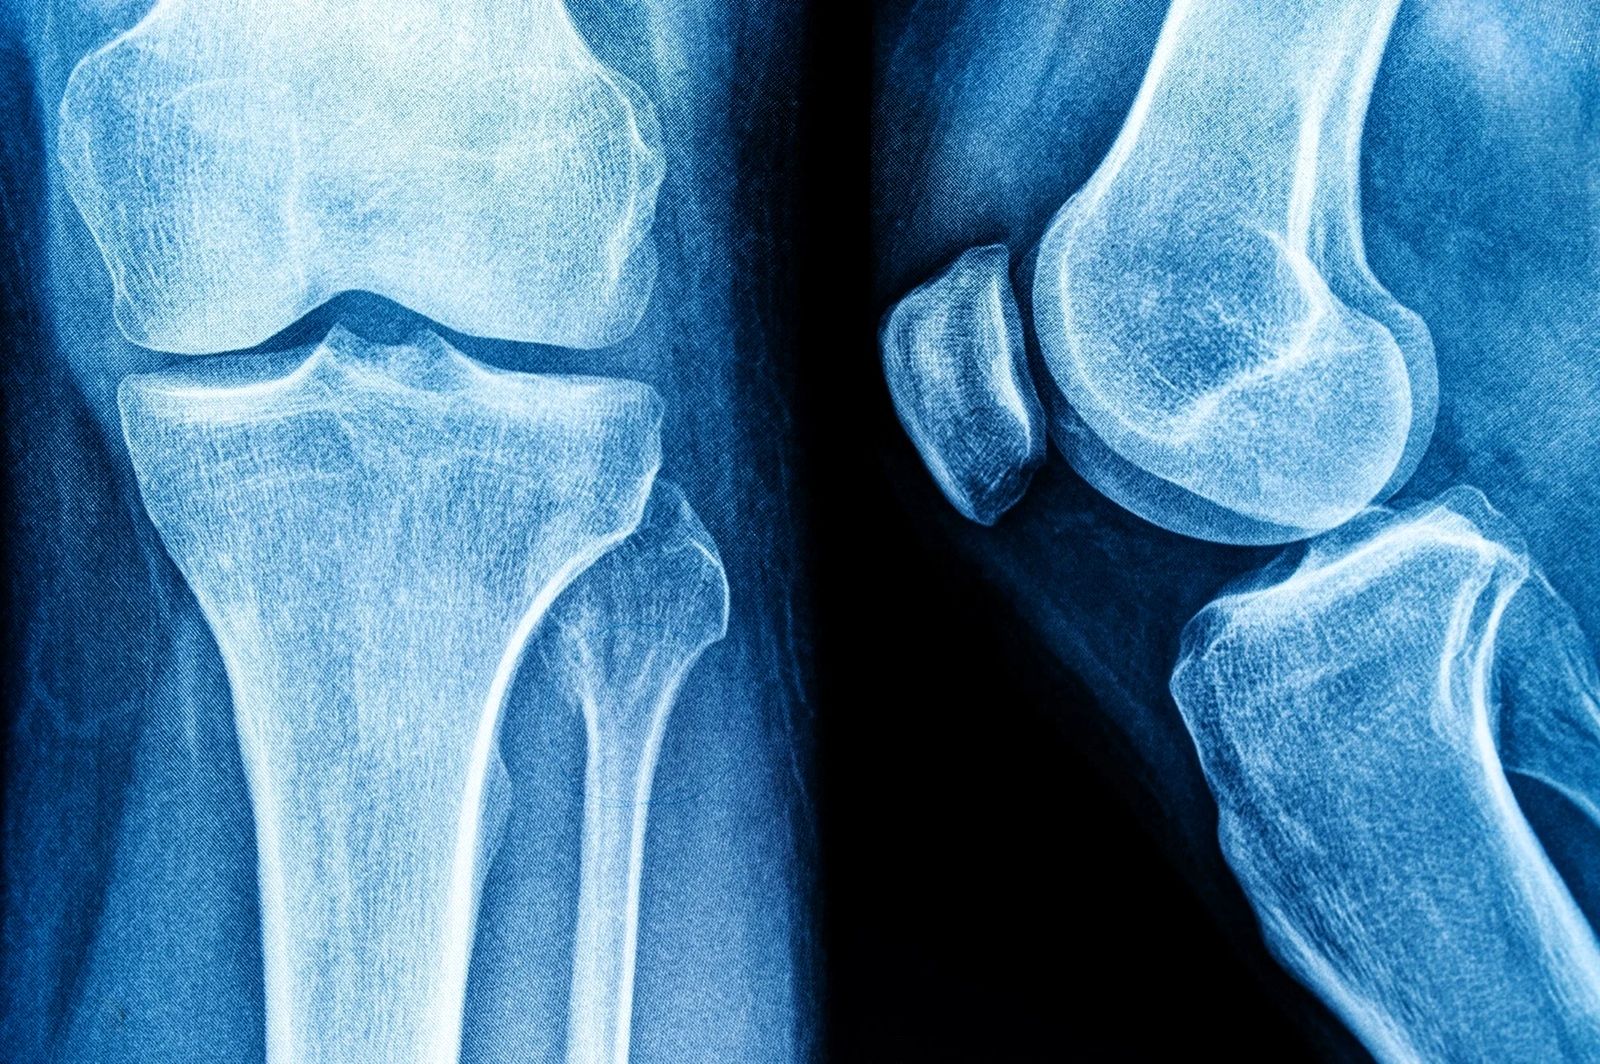

در دوران بزرگسالی، تشکیل استخوان کندتر و تجزیه‌ی استخوان سریع‌تر می‌شود که در نهایت می‌تواند منجر به کاهش توده‌ی استخوانی و افزایش خطر شکستگی‌های ناشی از شکنندگی شود. کلسیم، ویتامین D و فسفر برای سلامت و عملکرد استخوان‌ها ضروری هستند. ماست منبع خوبی از پروتئین، پتاسیم، کلسیم، ویتامین‌ها، روی و سلنیوم است؛ عناصری که همگی در تقویت و رشد استخوان نقش دارند.

به شکل خاص، یک مطالعه نشان داد مصرف مکرر ماست با کاهش خطر پوکی استخوان در استخوان زند زبرین (Radius) همراه است و مطالعه‌ای دیگر نشان داد زنانی که بیشترین مصرف ماست را داشتند، تراکم استخوان گردن فمور و مفصل ران بیشتری نسبت به گروه با کمترین مصرف داشتند. همچنین یک مطالعه دیگر ارتباطی ضعیف بین مصرف ماست و کاهش خطر شکستگی لگن یافت.

در فراتحلیل‌ها، هیچ ارتباط معنی‌داری بین مصرف ماست و خطر شکستگی لگن در سطوح گزارش‌شده‌ی مصرف مشاهده نشد. با این حال، مصرف ماست اثر مثبت ولی بسیار ناچیزی بر تراکم استخوان فمور داشت (SMD ≈ ۰.۰۰۹)، که از دید بالینی بی‌اهمیت تلقی می‌شود و نشان می‌دهد اثر آن بر سلامت اسکلت حداقلی است.